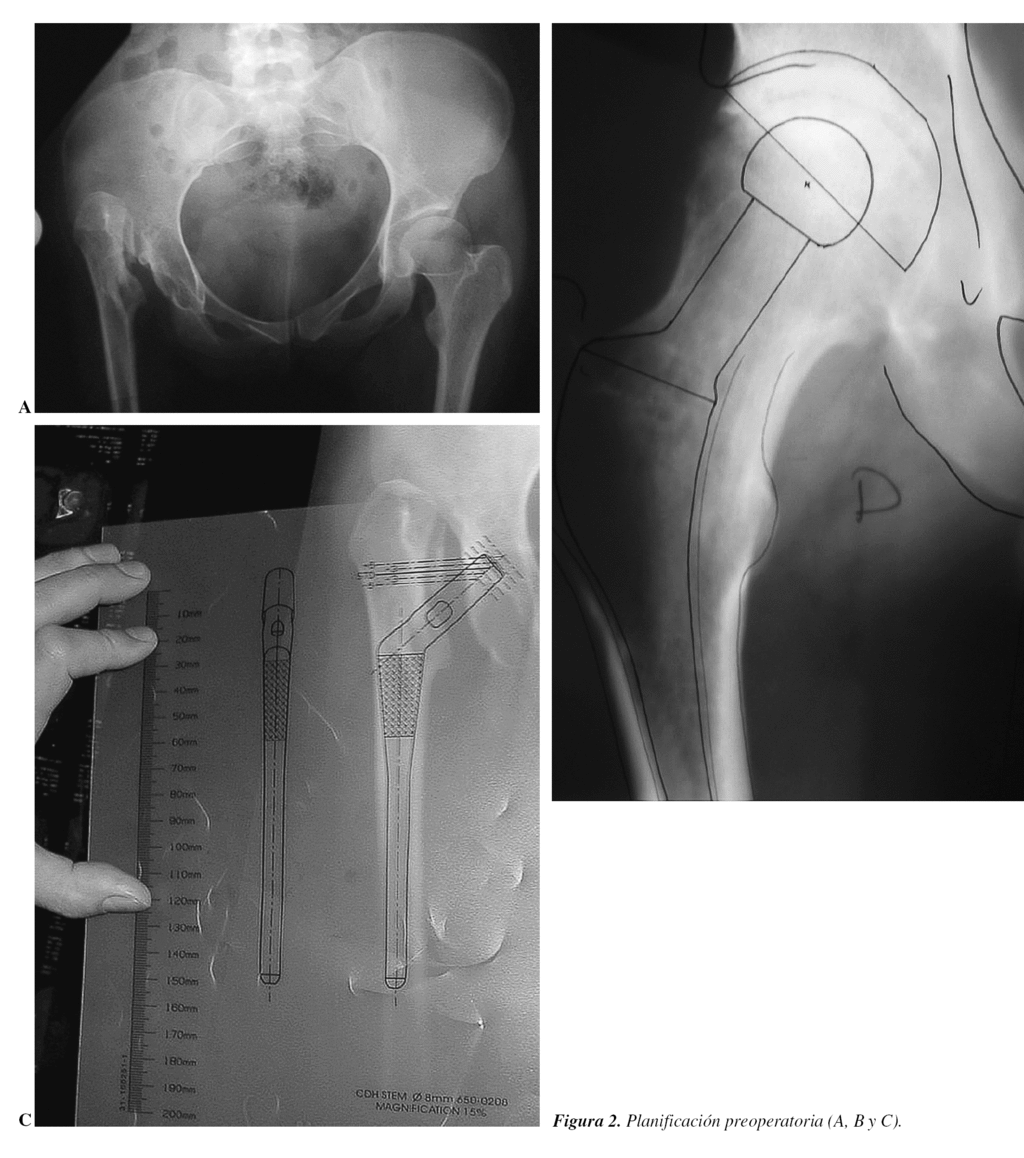

Son las primeras que hay que tener en cuenta y consisten en realizar una correcta planificación con las plantillas (figs. 2 y 3), con el fin de reproducir el acodo lo más exactamente posible, el centro de rotación de la cadera y la longitud del miembro9-12. Los pasos conocidos, pero que conviene recordar, son los siguientes:

5. Sobre la radiografía anteroposterior de la cadera se determina el tamaño apropiado, la posición y componente acetabular con las plantillas; después se marca el centro de rotación de la cadera.

Desde el punto de vista práctico, una planificación quirúrgica sería:

1. Nombre, apellidos y número de historia.

2. Edad y sexo.

3. Diagnóstico, tipo de implante cementado (sí/no, mixto).

4. Diferencia, si existe, de longitud de los miembros inferiores (MMII).

5. Cotilo: diámetro en mm, hemisférico, monobloque, perforado, insertos polietileno, cerámica, metal, tamaño interior.

6. Vástago: offset, número, si está cementado o no.

7. Corte del cuello a xx mm por encima del trocánter menor.

8. Longitud del cuello de más de 3,5 mm de diámetro; cabeza en mm metálica/cerámica.

9. Con esta reconstrucción se alarga o no el miembro.

10. Equipo especial que se puede necesitar: a) cotilos y fresas más pequeñas de lo habitual; b) cabezas de 26 mm de diámetro si hubiese que utilizar cotilos pequeños; c) cables de Dall-Miles o material de osteosíntesis en caso de fractura; d) instrumental específico para extraer implante; cortar cerámica, etc.